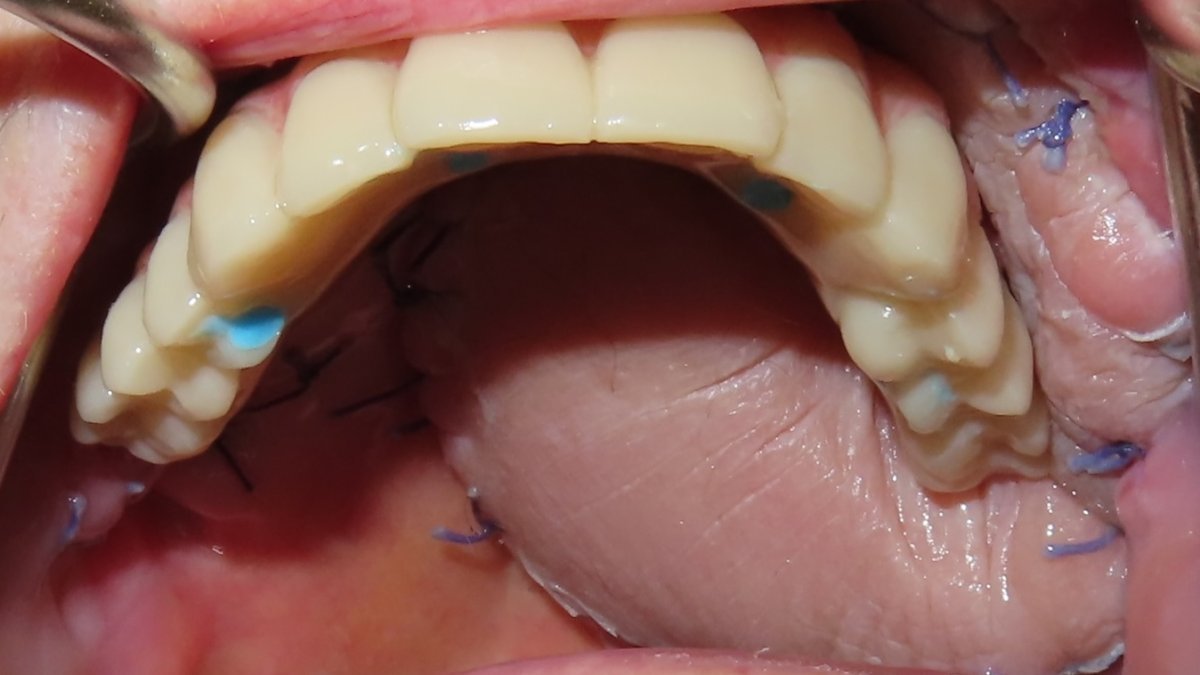

Initial prosthesis